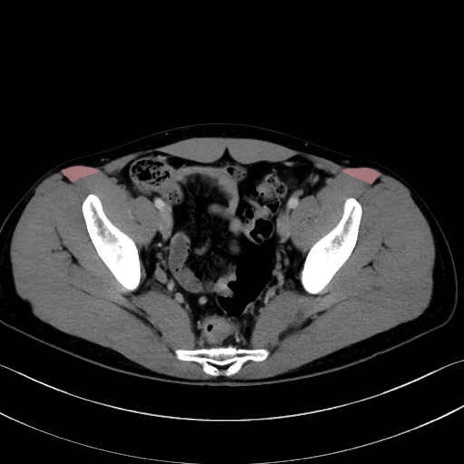

5. 大腿前面(大腿四頭筋群・伸筋群)

縫工筋 (Sartorius)

恥骨筋 (Pectineus)

長内転筋 (Adductor longus)